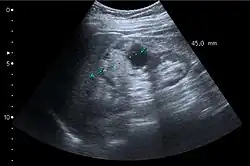

Renal ultrasonography

On renal ultrasonography, a solid renal mass appears in the US exam with internal echoes, without the well-defined, smooth walls seen in cysts, often with Doppler signal, and is frequently malignant or has a high malignant potential. The most common malignant renal parenchymal tumor is renal cell carcinoma (RCC), which accounts for 86% of the malignancies in the kidney. RCCs are typically isoechoic and peripherally located in the parenchyma, but can be both hypo- and hyper-echoic and are found centrally in medulla or sinus. The lesions can be multifocal and have cystic elements due to necrosis, calcifications and be multifocal (Figure 8 and Figure 9). RCC is associated with von Hippel–Lindau disease, and with tuberous sclerosis, and US has been recommended as a tool for assessment and follow-up of renal masses in these patients.[3]